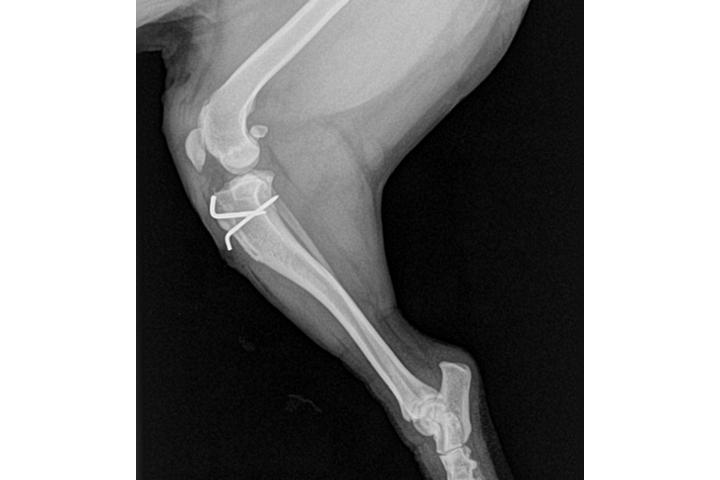

Rx de la rodilla de Snoopy tras la cirugía

Finalmente ya tengo en mi poder el informe quirúrgico y las radiografías del postoperatorio de Snoopy...las voy a publicar enseguida para que veáis la complejidad de la intervención y la sorprendente recuperación de esta maravillosa perrita....el jueves la llevamos a su primera revisión pero os aseguro que es increíble verla saltar y correr con su pAtita nueva....la otra pata ahora se la ve peor y es normal porque se le nota más la curvatura anormal de la luxación....calculamos que a este ritmo de la podrá operar de nuevo antes de lo que pensábamos. Ahora publicaré las radiografías y para el informe necesitaré ayuda porque está en mi mail en un formato raro y necesito a mi hermana y su ordenador....

Comparativa de las patas de Snoopy.